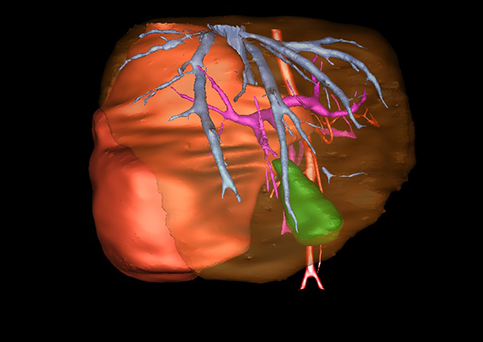

近年来由于数字医学的发展,基于可视化三维重建技术的计算机辅助手术系统极大推进了小儿肝脏肿瘤的精准手术的进步。可以立体透视肝脏解剖、精确掌握肝段的边界、精确测算肝段乃至任意血管所支配的功能体积、准确定位病灶及其与邻近血管的解剖关系,最终对不同手术方案进行比较、筛选和优化。因此,计算机辅助手术规划系统是实现精准肝切除的有力辅助工具,是未来数字外科、精准外科等21世纪外科新理念的重要技术支撑。

计算机辅助手术规划系统具有良好的操作可行性、计算准确性和三维显示效果,可半透明、交互式显示真实的肝内立体解剖关系和空间管道变异,准确计算肝内管道的直径、走行角度,两点间的垂直距离,和任意血管的支配或引流范围等传统二维影像无法获取的信息,有助于实施个体化手术,提高了手术的确定性、预见性和可控性。计算机辅助手术规划系统可直观显示预留肝脏的结构和功能,并可通过虚拟切割功能辅助术者对手术方案进行蹄选和优化,系统评估手术风险和制定对策,改变了部分二维规划的术式和切除范围,使部分二维规划认为不能切除的患者成功手术,提高了手术的根治性、安全性和病变的可切除性,更加符合精准肝脏外科的术前规划要求。详见第11章。

随着计算机技术及影像检查技术的不断发展,以精确的术前影像学和功能评估、精细的手术操作为核心的精准肝切除技术日益受到重视。基于数字医学的计算机辅助手术技术(computer-assisted surgery,CAS)则是实现肝脏精准手术操作的基础。计算机辅助手术系统(CAS)可将术前二维(two dimensional,2D)的CT/MRI影像数据进行三维(three dimensional,3D)重建,建立个体化的肝脏三维解剖模型,清晰显示肝脏内脉管系统的走行及解剖关系,还原病灶与其周围脉管结构的立体解剖构象,准确地对病变进行定位、定性和评估,制定合理、定量的手术方案,实施个体化的肝脏血管取舍分配方案及实施精准肝脏手术。一般认为CAS包括:创建虚拟的患者的图像;患者图像的分析与深度处理;诊断、手术前规划、手术步骤的模拟;术中实时导航。应用本技术后,由于可以更清晰地看出肿瘤的界限,特别是根据肝血管的显影,判断出肿瘤与门静脉及肝静脉的关系以在手术前较准确地估计出手术成功切除的可行性。以往部分根据普通强化CT判断无法手术的病例而被评估为可以成功切除并手术成功。